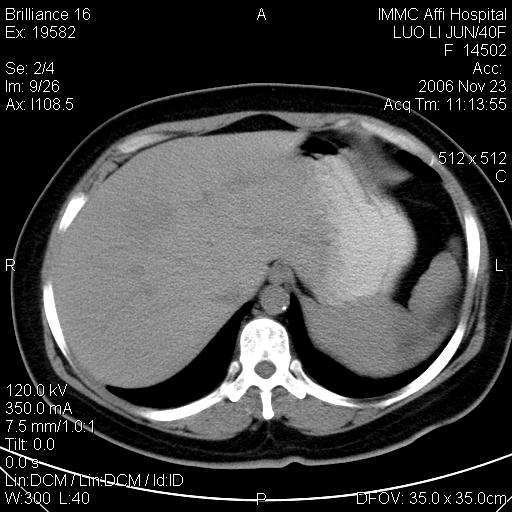

标题: CT5664:我也发一个肝脏的片子大家看看

很典型的肝癌。

典型肝癌

肝癌

速升速降,典型肝癌.

典型肝癌.

是啊,典型的早出早归!

快进快出典型肝癌.

符合肝癌的增强特征。支持肝癌!

病灶好圆!可能恶性度不高。

不能除外肝细胞腺瘤吧,还是得结合病史。

很好的片子,可惜增强做的比较失败,a期时间没有把我好,实际到了静脉早期了,否则会更典型。

最终考虑是肝腺瘤